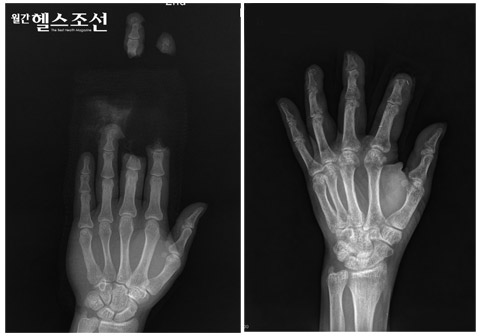

이미지

검지와 중지가 잘린 환자가 손가락접합수술을 받고 손가락 기능을 회복했다. 사진은 손가락이 절단된 상태에서 찍은 엑스레이(사진1)과 수술후 사진(사진2)다. (사진=조은선·임성필 St.HELLo)